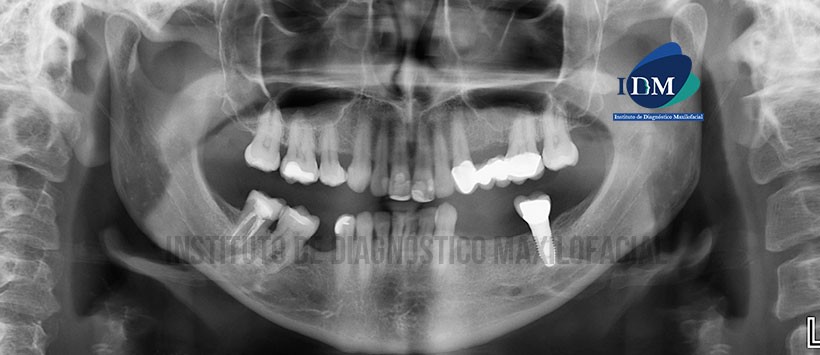

A la evaluación panorámica se aprecia neumatización alveolar de ambos senos maxilares, reabsorción ósea alveolar bimaxilar, edentulo parcial bimaxilar, múltiples restauraciones coronarias, pilares de puente protésico en piezas 23 y 26, implantes con prótesis sobre implante en pieza 37 y finalmente material de obturación de conductos en pieza 48. (Figura 1 )

Sin embargo en la evaluación mediante tomografía volumétrica de haz cónico (Figura 2 y Figura 3) se evidencio, que en ambas zonas parasinfisiarias, la presencia de dos agujeros mentonianos en ambos lados con desembocadura en la tabla ósea vestibular.